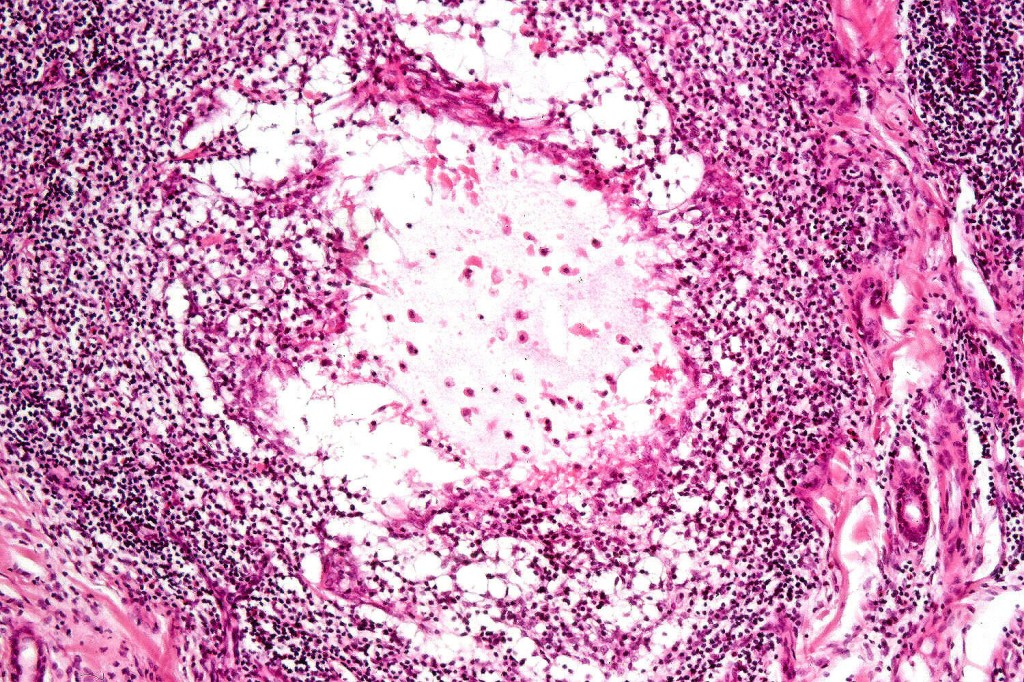

Histological features

•Follicular infiltration by atypical lymphocytes & Sézary cells

•Granulomatous inflammation secondary to follicular destruction

•Large cell transformation occasionally present